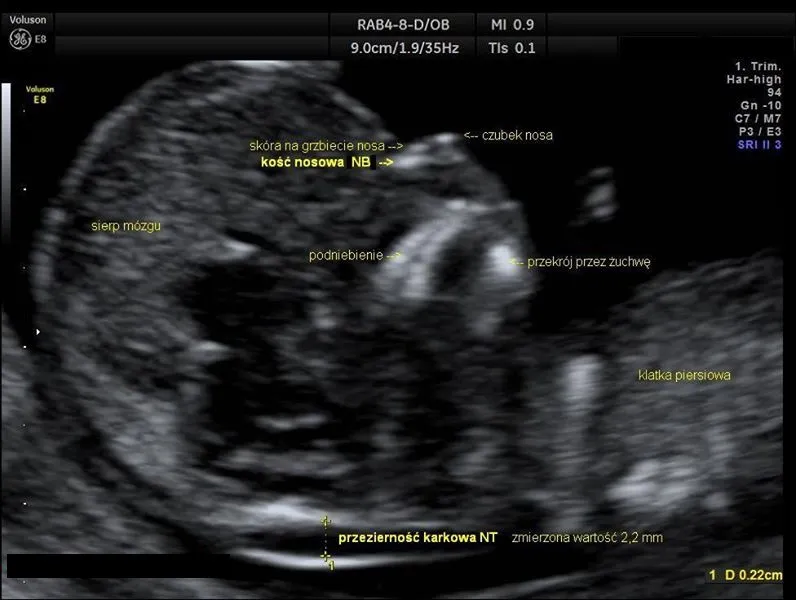

Przezierność karkowa (NT) i kość nosowa (NB): co oznaczają te parametry?

Podczas USG I trymestru oceniamy kilka kluczowych markerów. Najważniejszym z nich jest przezierność karkowa (NT), czyli pomiar płynu pod skórą na karku płodu. Zwiększona przezierność karkowa może wskazywać na podwyższone ryzyko wad genetycznych lub serca. Oceniamy również obecność kości nosowej (NB), której brak lub niedorozwój również może być markerem niektórych aberracji chromosomowych. Dodatkowo, zwracamy uwagę na przepływ krwi w przewodzie żylnym (DV) oraz na zastawce trójdzielnej (TR). Bardzo często to badanie jest elementem tzw. testu złożonego, łączonego z badaniem biochemicznym krwi matki (oznaczenie białka PAPP-A i wolnej podjednostki beta-hCG), co znacząco zwiększa jego czułość w wykrywaniu ryzyka wad.